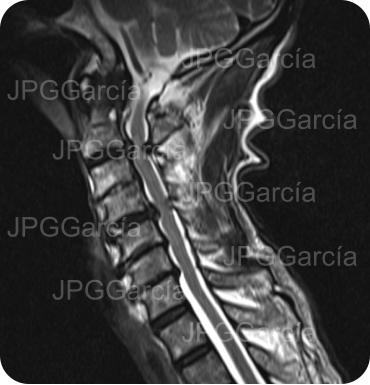

Tratamiento microquirúrgico de hernia extruida cervical con mielopatía

Estudios de control postquirúrgico radiográfico y de resonancia magnética